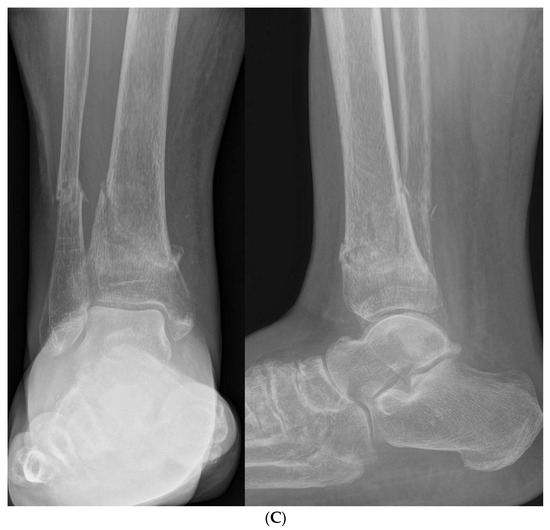

3.2.1. Osteochondritis Dissecans

- Perumal, V.; Wall, E.; Babekir, N. Juvenile osteochondritis dissecans of the talus. J. Pediatr. Orthop. 2007, 27, 821–825. [Google Scholar] [CrossRef] [PubMed]

- Letts, M.; Davidson, D.; Ahmer, A. Osteochondritis dissecans of the talus in children. J. Pediatr. Orthop. 2003, 23, 617–625. [Google Scholar] [CrossRef]